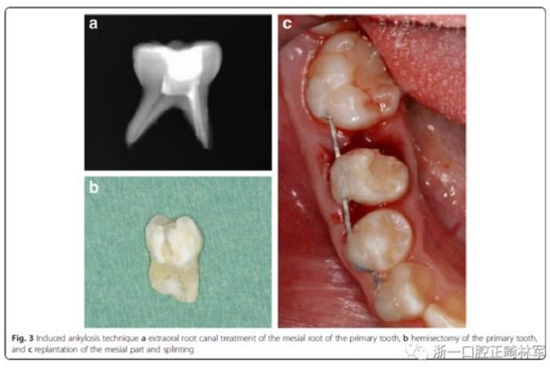

牙槽固連技術(shù)包括在局麻下拔除乳磨牙,然后進(jìn)行近中根的體外根管治療,對(duì)牙冠做復(fù)合樹(shù)脂的修復(fù),進(jìn)行2mm的根尖切除術(shù)和偏側(cè)牙根切除。為了達(dá)成牙槽固連,我們采用了根尖孔閉合且在口外干燥60分鐘以上脫位牙的處理方法。用刮治器從根面上收集牙周膜細(xì)胞。拔除6分鐘后,用鹽溶液沖洗牙槽窩,將近中牙根帶輕微壓力重新植入。為了保持牙齒穩(wěn)定,從右側(cè)尖牙到右側(cè)第一磨牙應(yīng)用0.016’’*0.022’’不銹鋼方絲作為牙弓夾板。